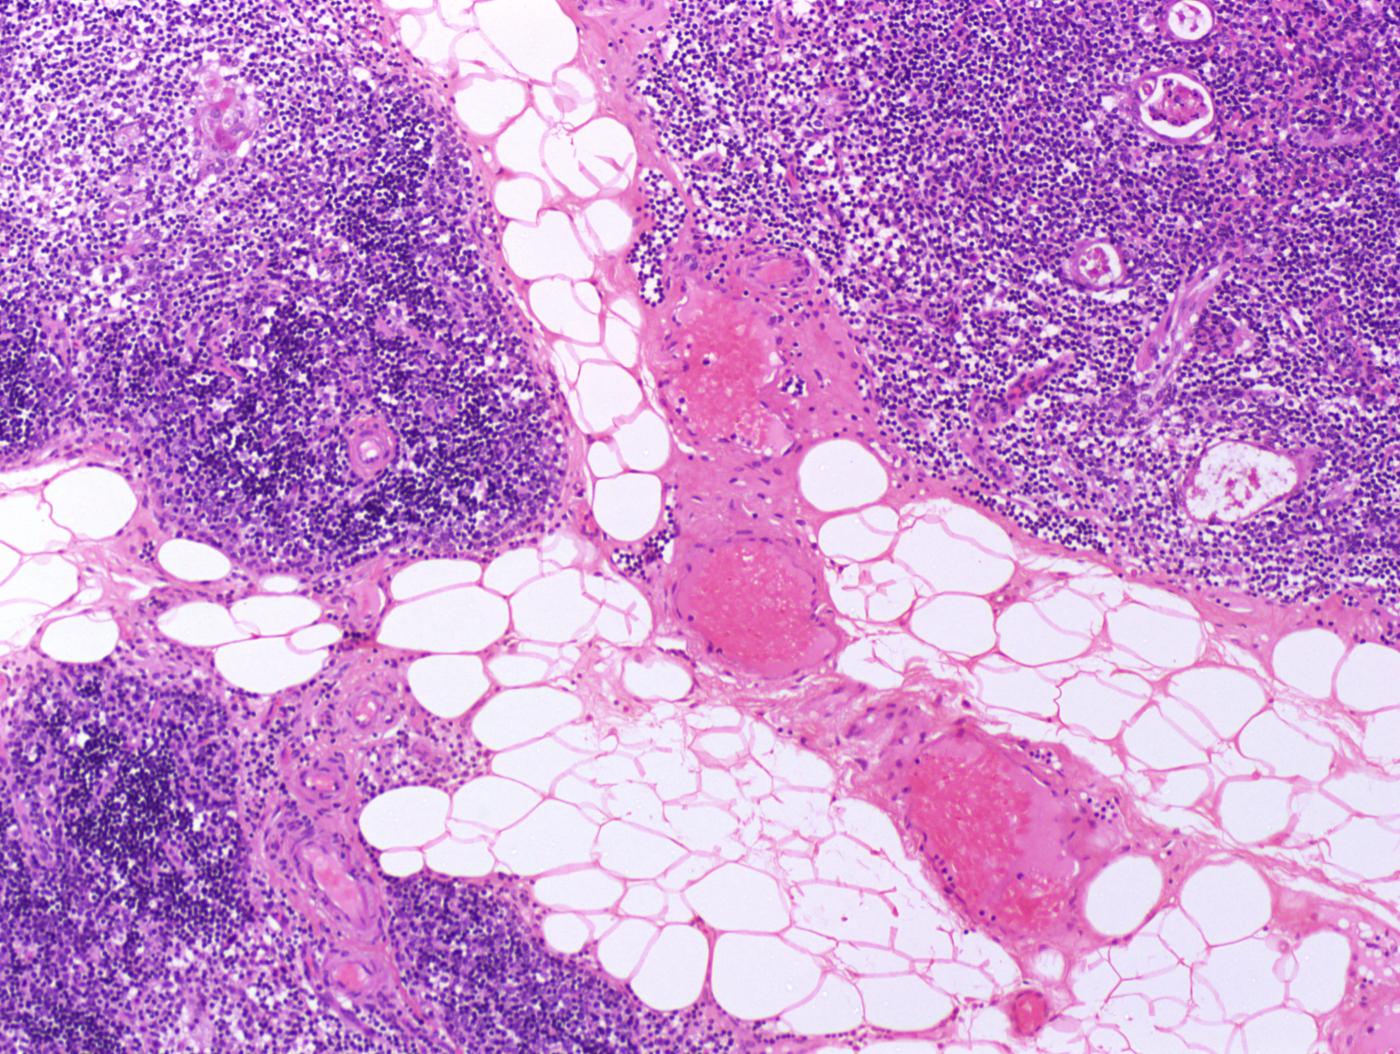

El diagnòstic de l’MG es basa en els símptomes, l’examen físic i les exploracions paraclíniques, en què les proves de més pes específic són l’electromiograma (EMG i SF-EMG) i el test d’edrofoni (Tensilón®). En la majoria de pacients és possible identificar la presència d’anticossos (AChR i MuSK) en sèrum. Un petit percentatge de pacients són seronegatius per a aquests anticossos. L’estudi s’ha de completar fent una tomografia computada (TC) per descartar la presència d’un timoma.

L’extirpació quirúrgica de la glàndula del tim (timectomia) pot millorar els símptomes, prevenir un cert nombre de complicacions al llarg de la vida i reduir la dosi de medicaments immunosupressors. La timectomia es recomana en formes generalitzades d’MG en pacients menors de 55 anys i en tots els pacients amb timoma, independentment de l’edat.